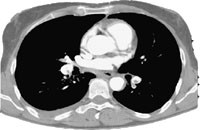

Røntgen thorax viste venstresidig pleuraadheranse. Ultralydundersøking av venstre underekstremitet viste trombe i v. femoralis communis med proksimal grense i v. iliaca externa. Pulmonal angiografi viste ein stor embolus i overgangen mellom greinene til venstre underlapp og lingula, utan kontrastfylling av segmentgreinene til øvre del av underlappen (fig 3). I samme seanse blei det utført kateterdirigert, lokal trombolyse (tab 1).

Ved kontroll dagen etter var det ein liten resttrombe i arterien til venstre underlapp, men det meste av tromben var lysert. Segmentgreinene til underlappen var opne (fig 4). Behandlinga blei avslutta. Ultralydundersøking tre dagar etterpå viste at tromben i v. iliaca externa og v. femoralis communis sinistra var borte.